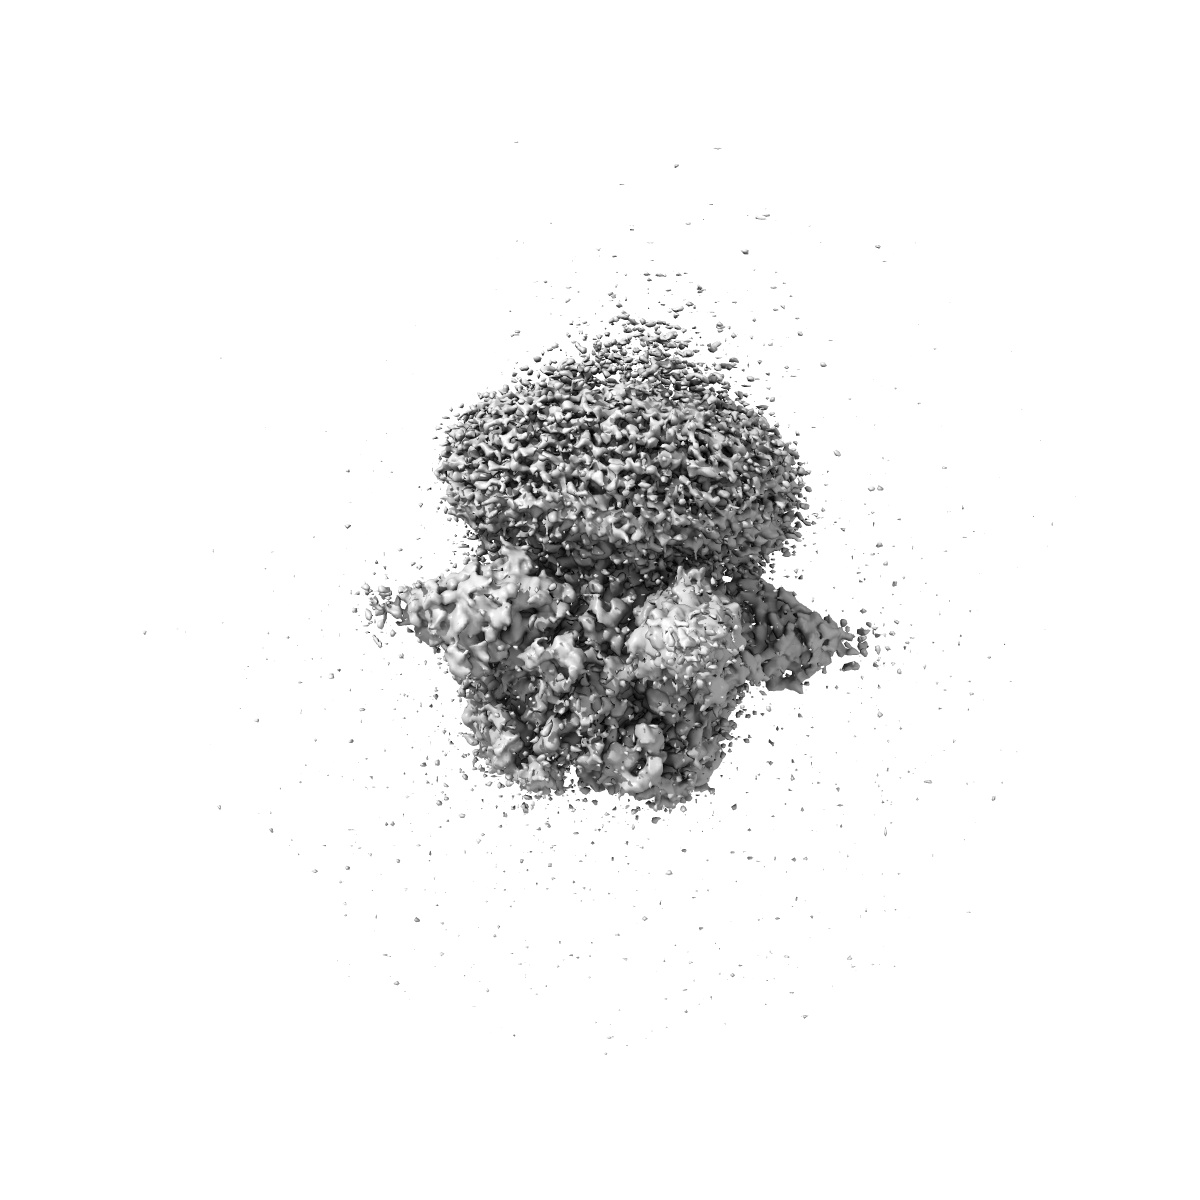

Cryo-EM structure of human full-length beta3delta GABA(A)R in complex with nanobody Nb25

Single-particle2.9 Å

Sample: Human full-length beta3delta GABA(A)R in complex with Nanobody Nb25